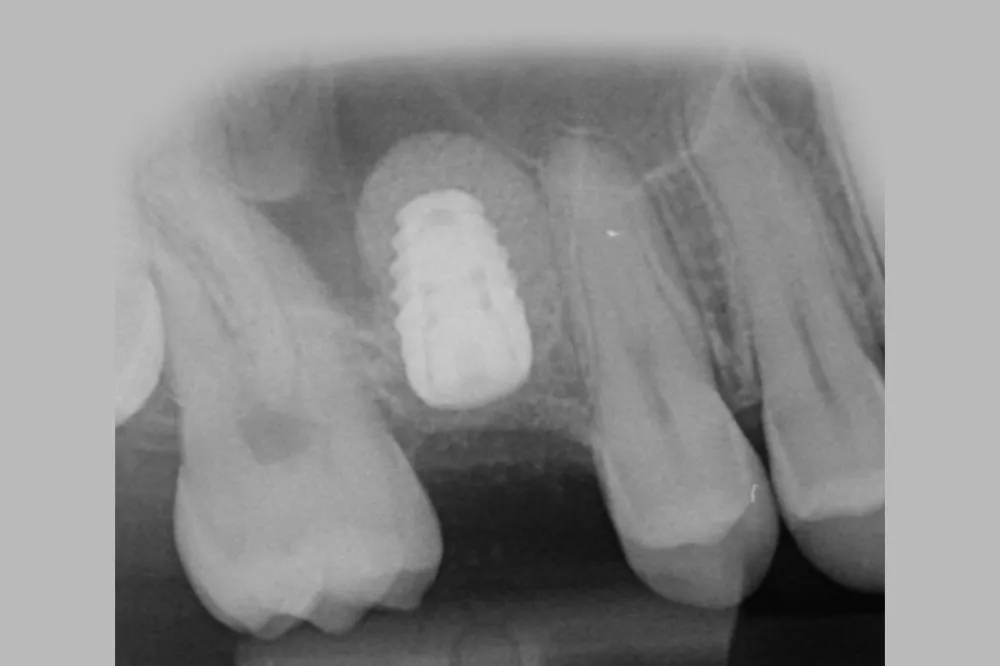

Los estudios disponibles muestran tasas de perforación inferiores al 10% y tasas de éxito cercanas al 97%, incluso en casos con altura ósea residual limitada (figuras 3, 4, 5, 6 y 7).

Fig. 4. Elevación de seno cerrada eficiente. 0,25cc de Biomaterial e implante dental

Fig. 6. Secuencia de elevación sinusal cerrada. Elevación y compactación del biomaterial

Fig. 7. Elevación sinusal cerrada e implante dental insertado en un solo acto.